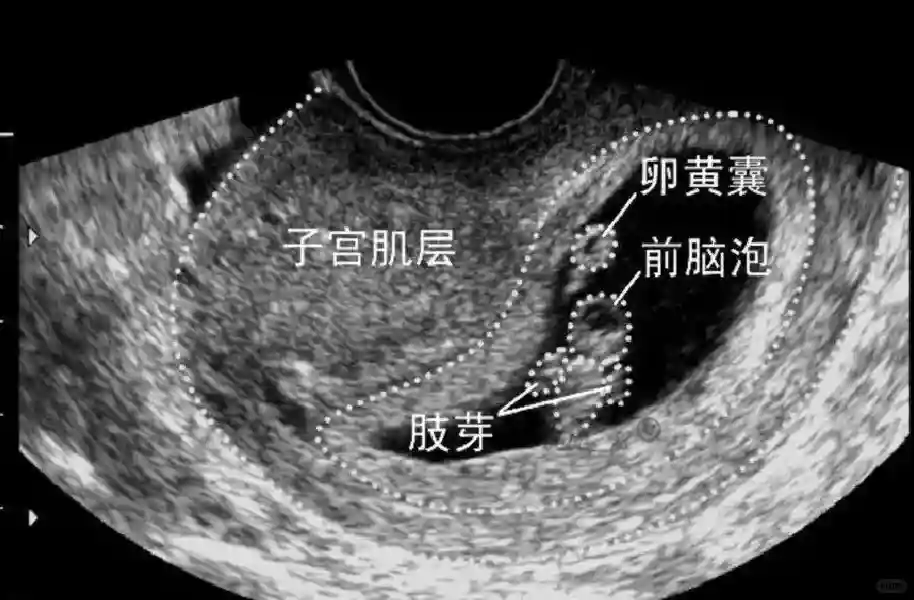

2️⃣卵黄囊:是妊娠囊内第一个解剖结构,直径<7mm。表现为小环状,中央为无回声,囊壁薄,内透声好。卵黄囊位于胚胎旁胚外体腔内。卵黄囊通常在孕5-6周时出现,5-10周稳步增长,一般不超过7mm,至12周消失。妊娠囊的大小与卵黄囊之间有一定关系,妊娠囊平均直径> 8 mm 时,经阴道超声均应显示卵黄囊,妊娠囊平均直径> 18 mm 时,经腹超声均应显示卵黄囊。

3️⃣胚胎:胚胎通常在6-7周时可以为超声显示,起初为胎芽,表现为卵黄囊一侧局部组织增厚,达到1 -2 mm 时才有可能为超声测量出来。达4-5mm时可见胎心搏动,相应孕周为6-6.5周,妊娠囊大小为13-18mm。胚芽长度≥7㎜时仍未见心管搏动,提示胚胎停止发育。胚胎的出现和妊娠囊直径的关系:妊娠囊直径> 16 mm 时,经阴道超声应显示胚胎。妊娠囊直径> 25 mm 时,经腹超声均应显示胚胎。

5️⃣羊膜:早孕期羊膜囊菲薄,超声常不能显示。孕7周以后加大增益或者用高频超声可以显示羊膜。羊膜囊位于绒毛膜内,胚胎位于羊膜囊内。随着胚胎增长,羊水增多,羊膜囊增大,孕12-16周时,羊膜与绒毛膜全部融合,胚外体腔消失。宫腔线一侧内膜内一圆形增强回声区,中央有小囊状液性暗区,宫腔线局部突起变形,称蜕膜内征,用于判断早早孕。#超声 #早孕检查 #妊娠